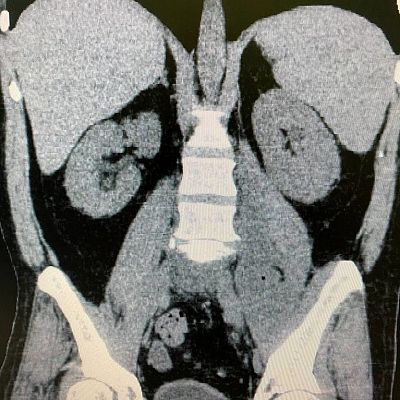

При дообследовании в стационаре выявлены высокие показатели маркеров воспаления, указывающие на септическое состояние пациента, плюс усиливающиеся боли… Дальнейшее обследование мужчина уже проходил в реанимации. По результатам компьютерной томографии у него выявлен ранее перенесенный перелом суставных отростков 4-го поясничного позвонка и абсцесс в структуре правой поясничной мышцы - источник сепсиса установлен. Именно этот абсцесс доставлял пациенту столько страданий и даже мешал лежать на спине.

«Вскрытие гнойных полостей в этой анатомической области представляет значительные трудности для хирурга и большой травматизм операции для пациента, - говорит проводивший операцию заведующий отделением экстренной хирургии Артем Александрович Косов. - В виду чего было принято решение о попытке минимально инвазивного вмешательства, избежав полостной операции с неизбежным рассечением мышечной ткани. Мы нашли небольшое ультразвуковое окно, позволяющее произвести дренирование указанного абсцесса, через переднюю брюшную стенку, при этом не затрагивая брюшную полость».

Ювелирно, под местной анестезией и в миллиметровой близости от магистральных сосудов (подвздошные артерия и вена проходили в 3 мм от места пункции) и сигмовидной кишки (расстояние до нее составляло 5 мм), наши врачи под УЗИ-контролем выполнили пункционное дренирование полости абсцесса, эвакуировав 400 мл гноя!